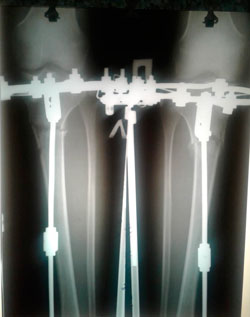

Исходник - 22 года. Павлодар.

Дата операции - 19.06.2018г.

Ротация справа.